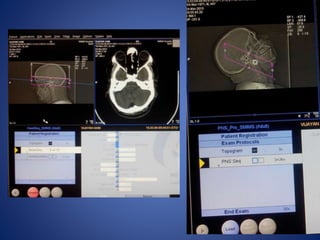

CONSOLE

CT IMAGES

Windowing- the term used for the method of varying density and contrast.

Window width-range of CT numbers we select for display

Window level-is usually but not always, the central CT number about which the window is chosen